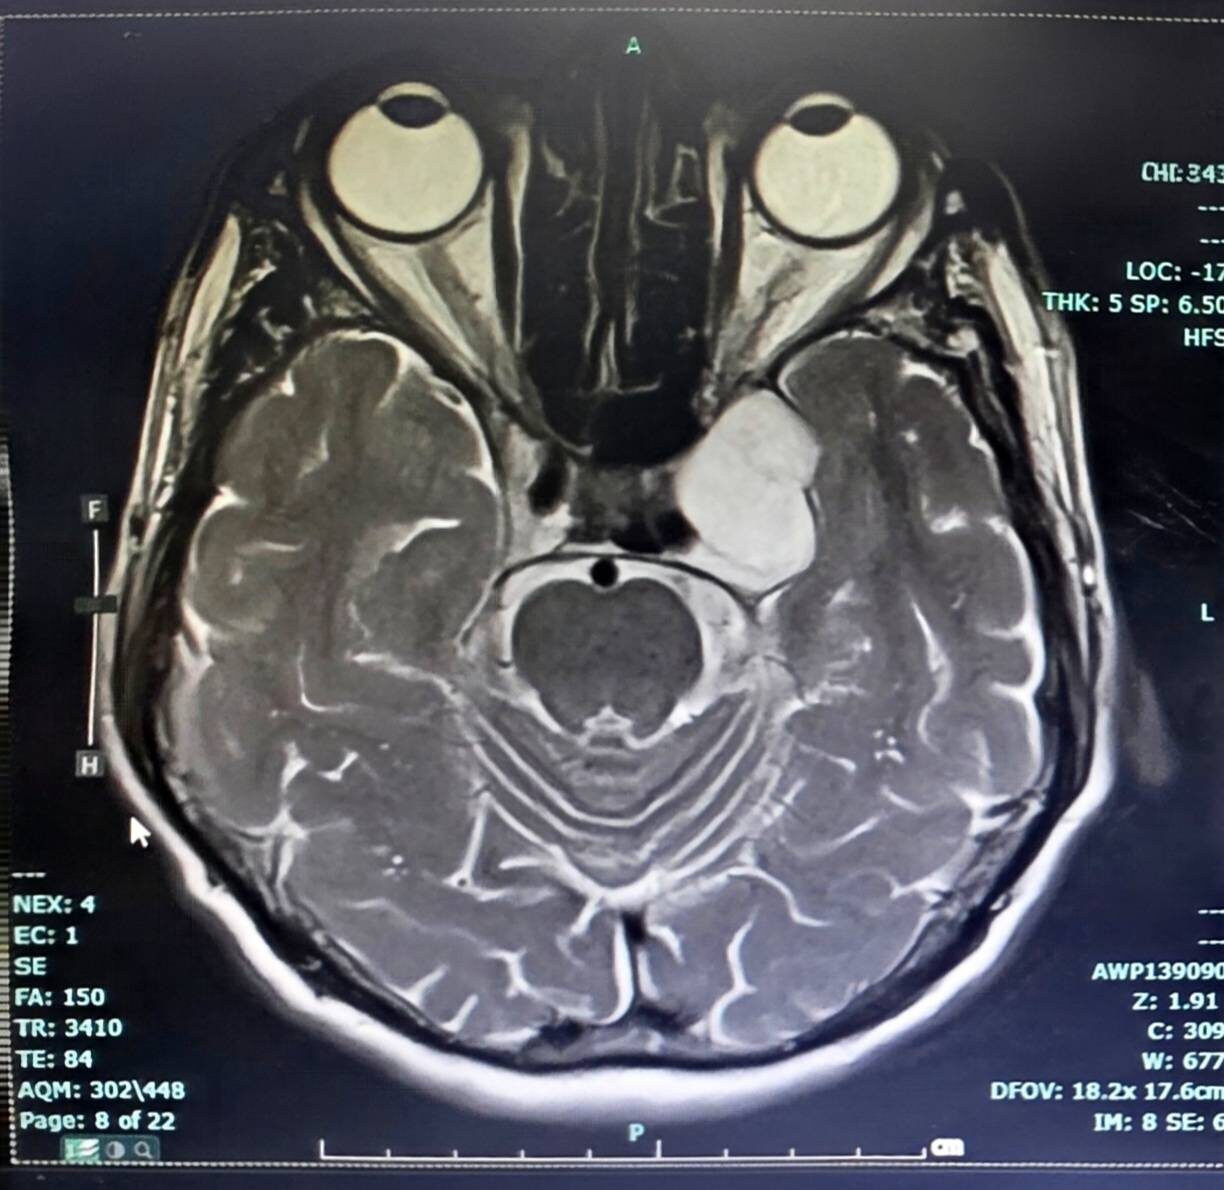

วันที่ 26 มี.ค.2569 เพจ โรงพยาบาลลำปาง Lampang Hospital โพสต์ข้อความประสบความสำเร็จในการรักษาผู้ป่วย ความว่า ในวันที่ 24 มีนาคม 2569 โรงพยาบาลลำปาง ประสบความสำเร็จในการผ่าตัดเนื้องอกฐานสมอง (Skull Base Surgery) บริเวณโพรงไซนัสคาเวอร์นัส (Cavernous Sinus Tumor) ด้วยเทคนิค Endoscopic Transorbital Approach (ETOA) ซึ่งเป็นการผ่าตัดผ่านกล้องส่องทางเบ้าตา

จัดเป็นการผ่าตัดแผลเล็ก (Minimal Invasive Surgery) เป็นเทคโนโลยีศัลยกรรมขั้นสูงที่ช่วยลดการบาดเจ็บต่อสมองและโครงสร้างสำคัญ เมื่อเทียบกับการผ่าตัดแบบเปิดกะโหลกขนาดใหญ่ และนับได้ว่าเป็นการผ่าตัด ETOA เพื่อผ่าตัดเนื้องอกสมอง สำเร็จเป็นเคสแรกของเขตสุขภาพที่ 1 กระทรวงสาธารณสุข

การผ่าตัดดำเนินการโดย นพ.เอื้ออังกูรยิ์ สิทธิมงคล ศัลยแพทย์ระบบประสาท โรงพยาบาลลำปาง การผ่าตัดเป็นไปอย่างราบรื่น สามารถนำก้อนเนื้องอกออกได้สำเร็จ หลังผ่าตัดผู้ป่วยฟื้นตัวดี และสามารถกลับมาใช้ชีวิตประจำวันได้ตามปกติ